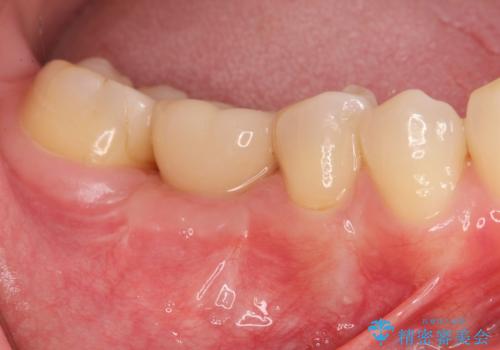

[ 臼歯部インプラント治療 ] 抜けた歯を治療したい

![[ 臼歯部インプラント治療 ] 抜けた歯を治療したいの症例 治療後](https://seimitsushinbi.jp/wp/wp-content/uploads/2022/06/3d94cd3d2c3bb38c4cb75b95fbdde67e-500x350.jpg?v=1655972093)